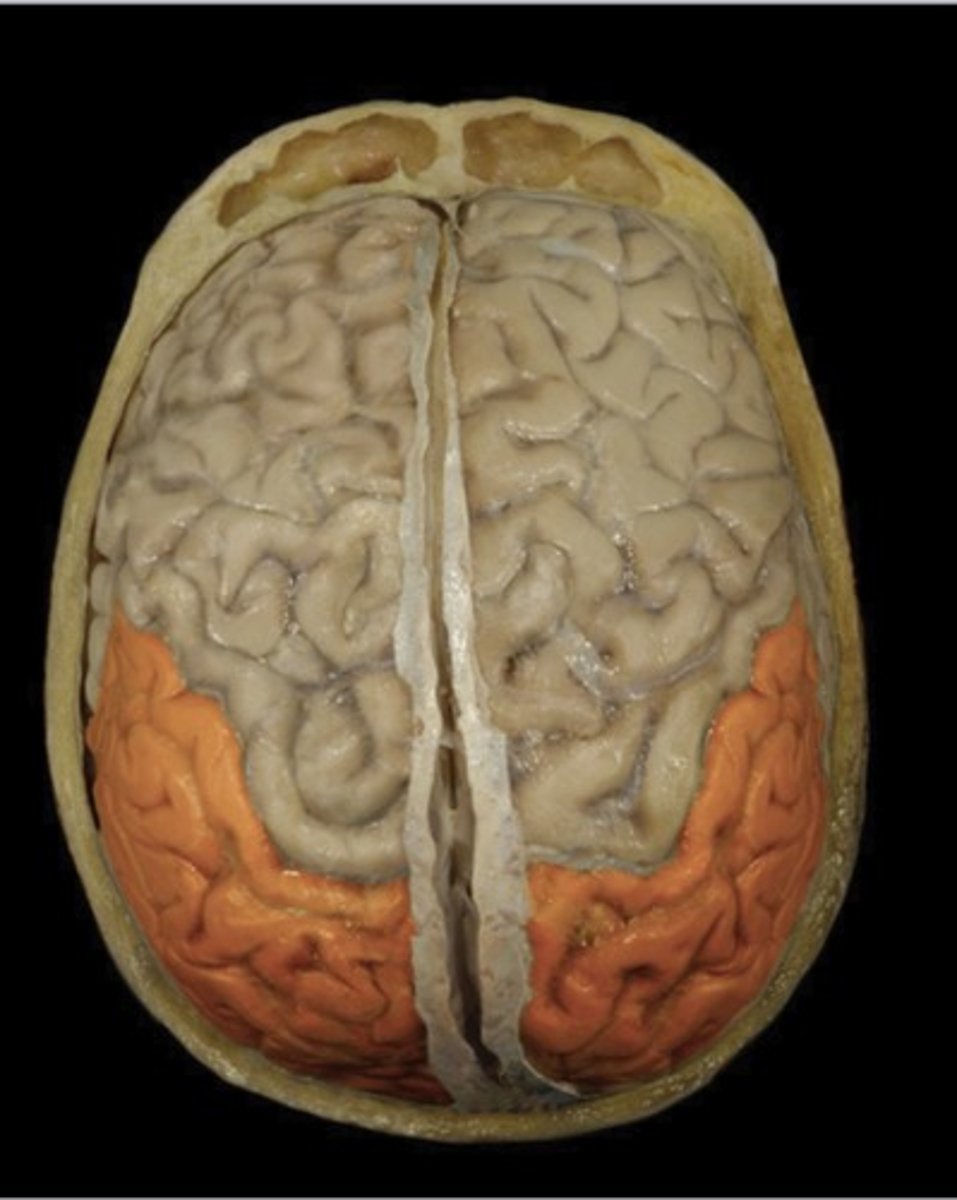

Precentral Gyrus (superior view)

Name this structure

Postcentral Gyrus (superior view)

Name this structure

Frontal Lobe (superior view)

Name this structure

Occipital Lobe (superior view)

Name this structure